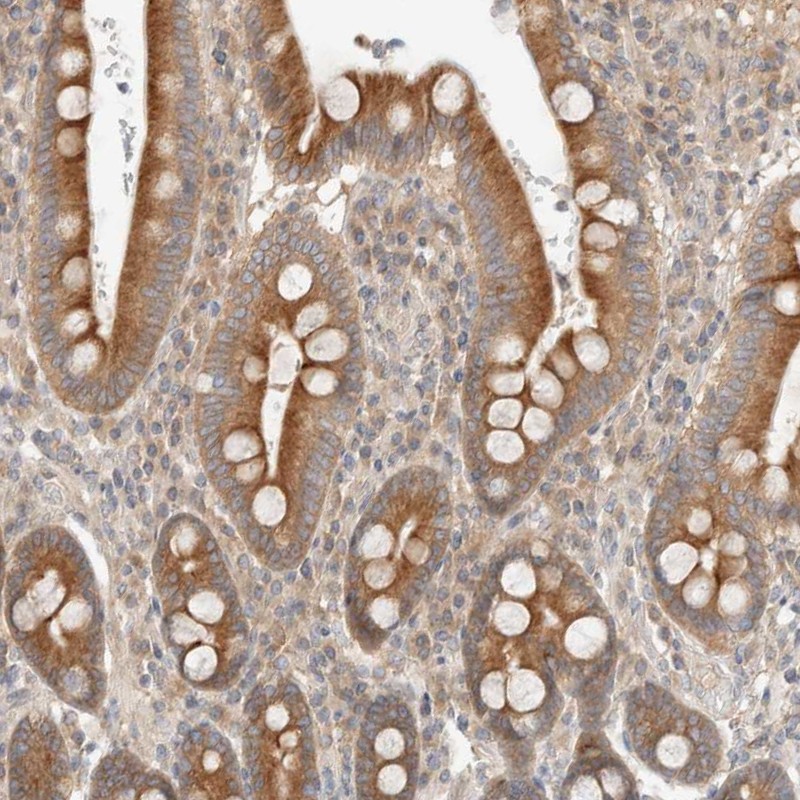

Immunohistochemical staining of human duodenum shows strong cytoplasmic positivity in glandular cells.